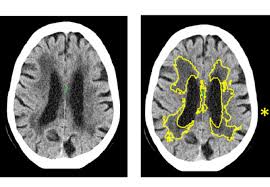

For the first time, the researchers indicate that it may be possible to reduce the risk of young-onset dementia, which occurs when a person develops the disorder affecting their memory, thinking, and social abilities before the age of 65, by targeting health and lifestyle factors.

The study showed that lower formal education, lower socioeconomic status, genetic variation, lifestyle factors such as alcohol use disorder and social isolation, and health issues including vitamin D deficiency, depression, stroke, hearing impairment, and heart disease significantly elevate the risk of young-onset dementia.